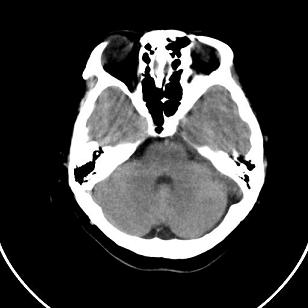

小脑后的囊状低密度影,里面可见分隔,考虑枕大池还是蛛网膜囊肿。

双侧脑室外缘灰质密度结节应该是尾状核的体部;枕大池前缘受压前移位,考虑囊肿

支持灰质移位,mri检查有必要.枕大池蛛网膜囊肿.

1)脑灰质异位。2)双侧枕部颅骨内板下方类似扇形及弧形脑脊样低密度影;鉴别于巨大枕大池与蛛网膜囊肿之间。建议必要时行进一步检查。

支持 1灰质移位,2枕大池蛛网膜囊肿。